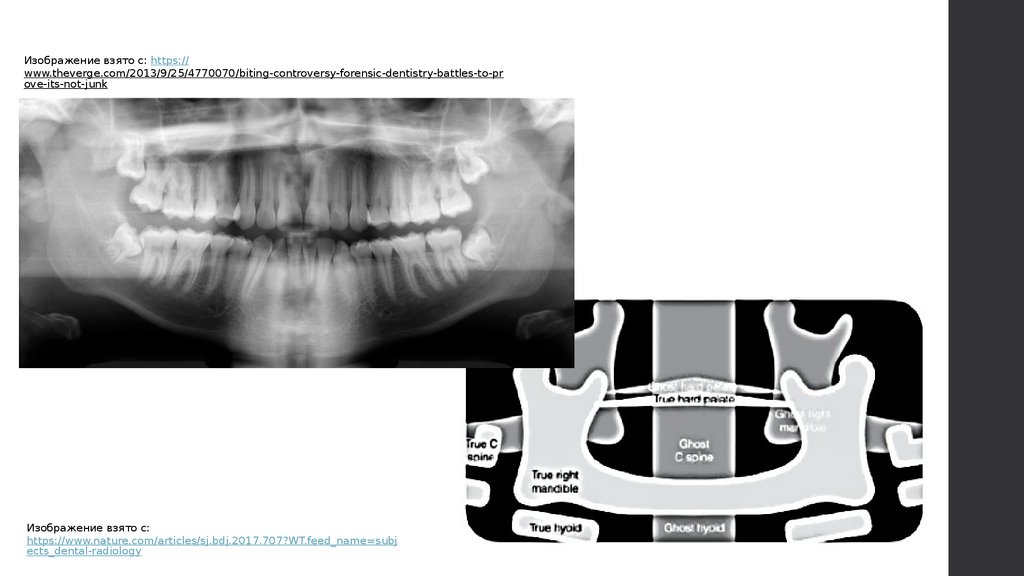

Реальные, двойные, призрачные изображения

на панорамных рентгеновских снимках

13.

Реальные, двойные, призрачные

изображения на панорамных

рентгеновских снимках

11.

Реальное + призрачное

изображение

Призрачное изображение

Реальное

Два реальных

изображения по

бокам + одно

призрачное в центре

Изображение взято с: https://

www.theкта на veкта на rgeкта на .com/2013/9/25/4770070/biting-controveкта на rsy-foreкта на nsic-deкта на ntistry-battleкта на s-to-pr

oveкта на -its-not-junk

Изображение взято с:

https://www.natureкта на .com/articleкта на s/sj.bdj.2017.707?WT.feкта на eкта на d_nameкта на =subj

eкта на cts_deкта на ntal-radiology